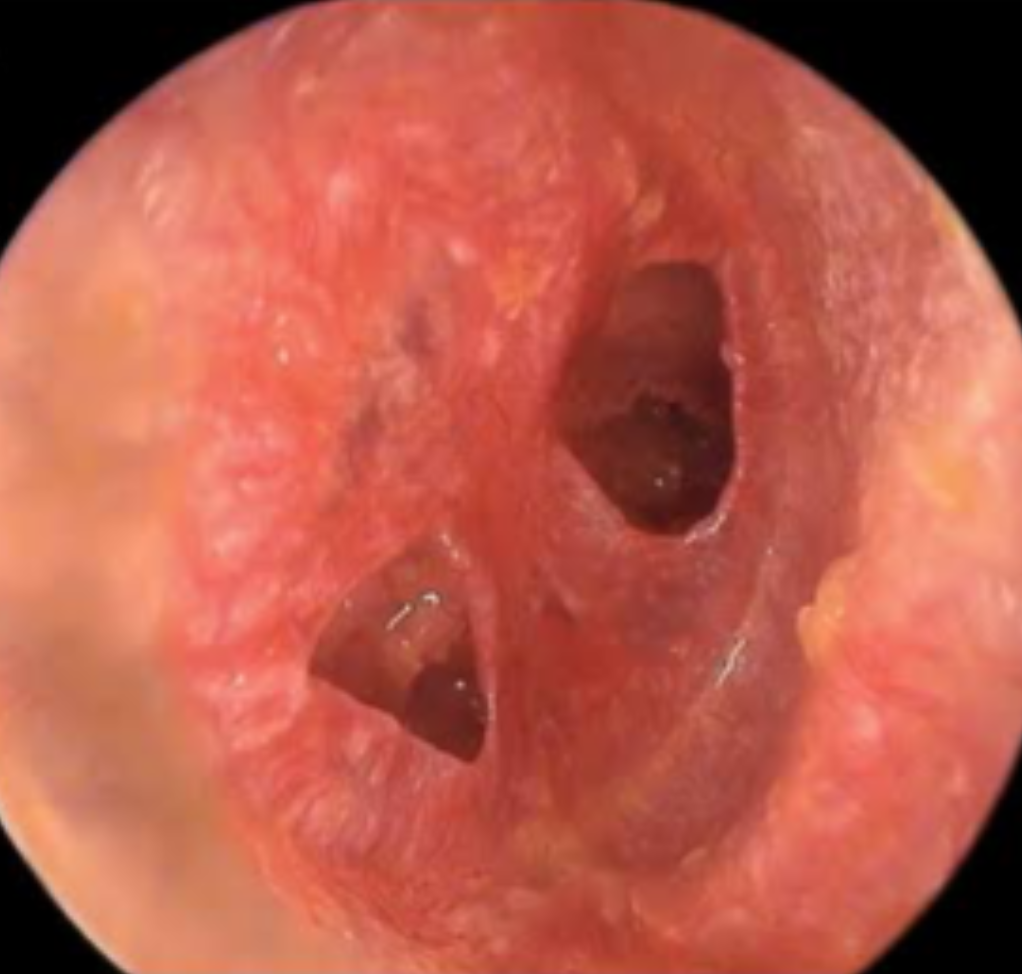

Signs of ear canal and eardrum problems

Look at these pictures of the inside of the ear. Do they look healthy?

No, there are two holes in the eardrum and it is red in colour.